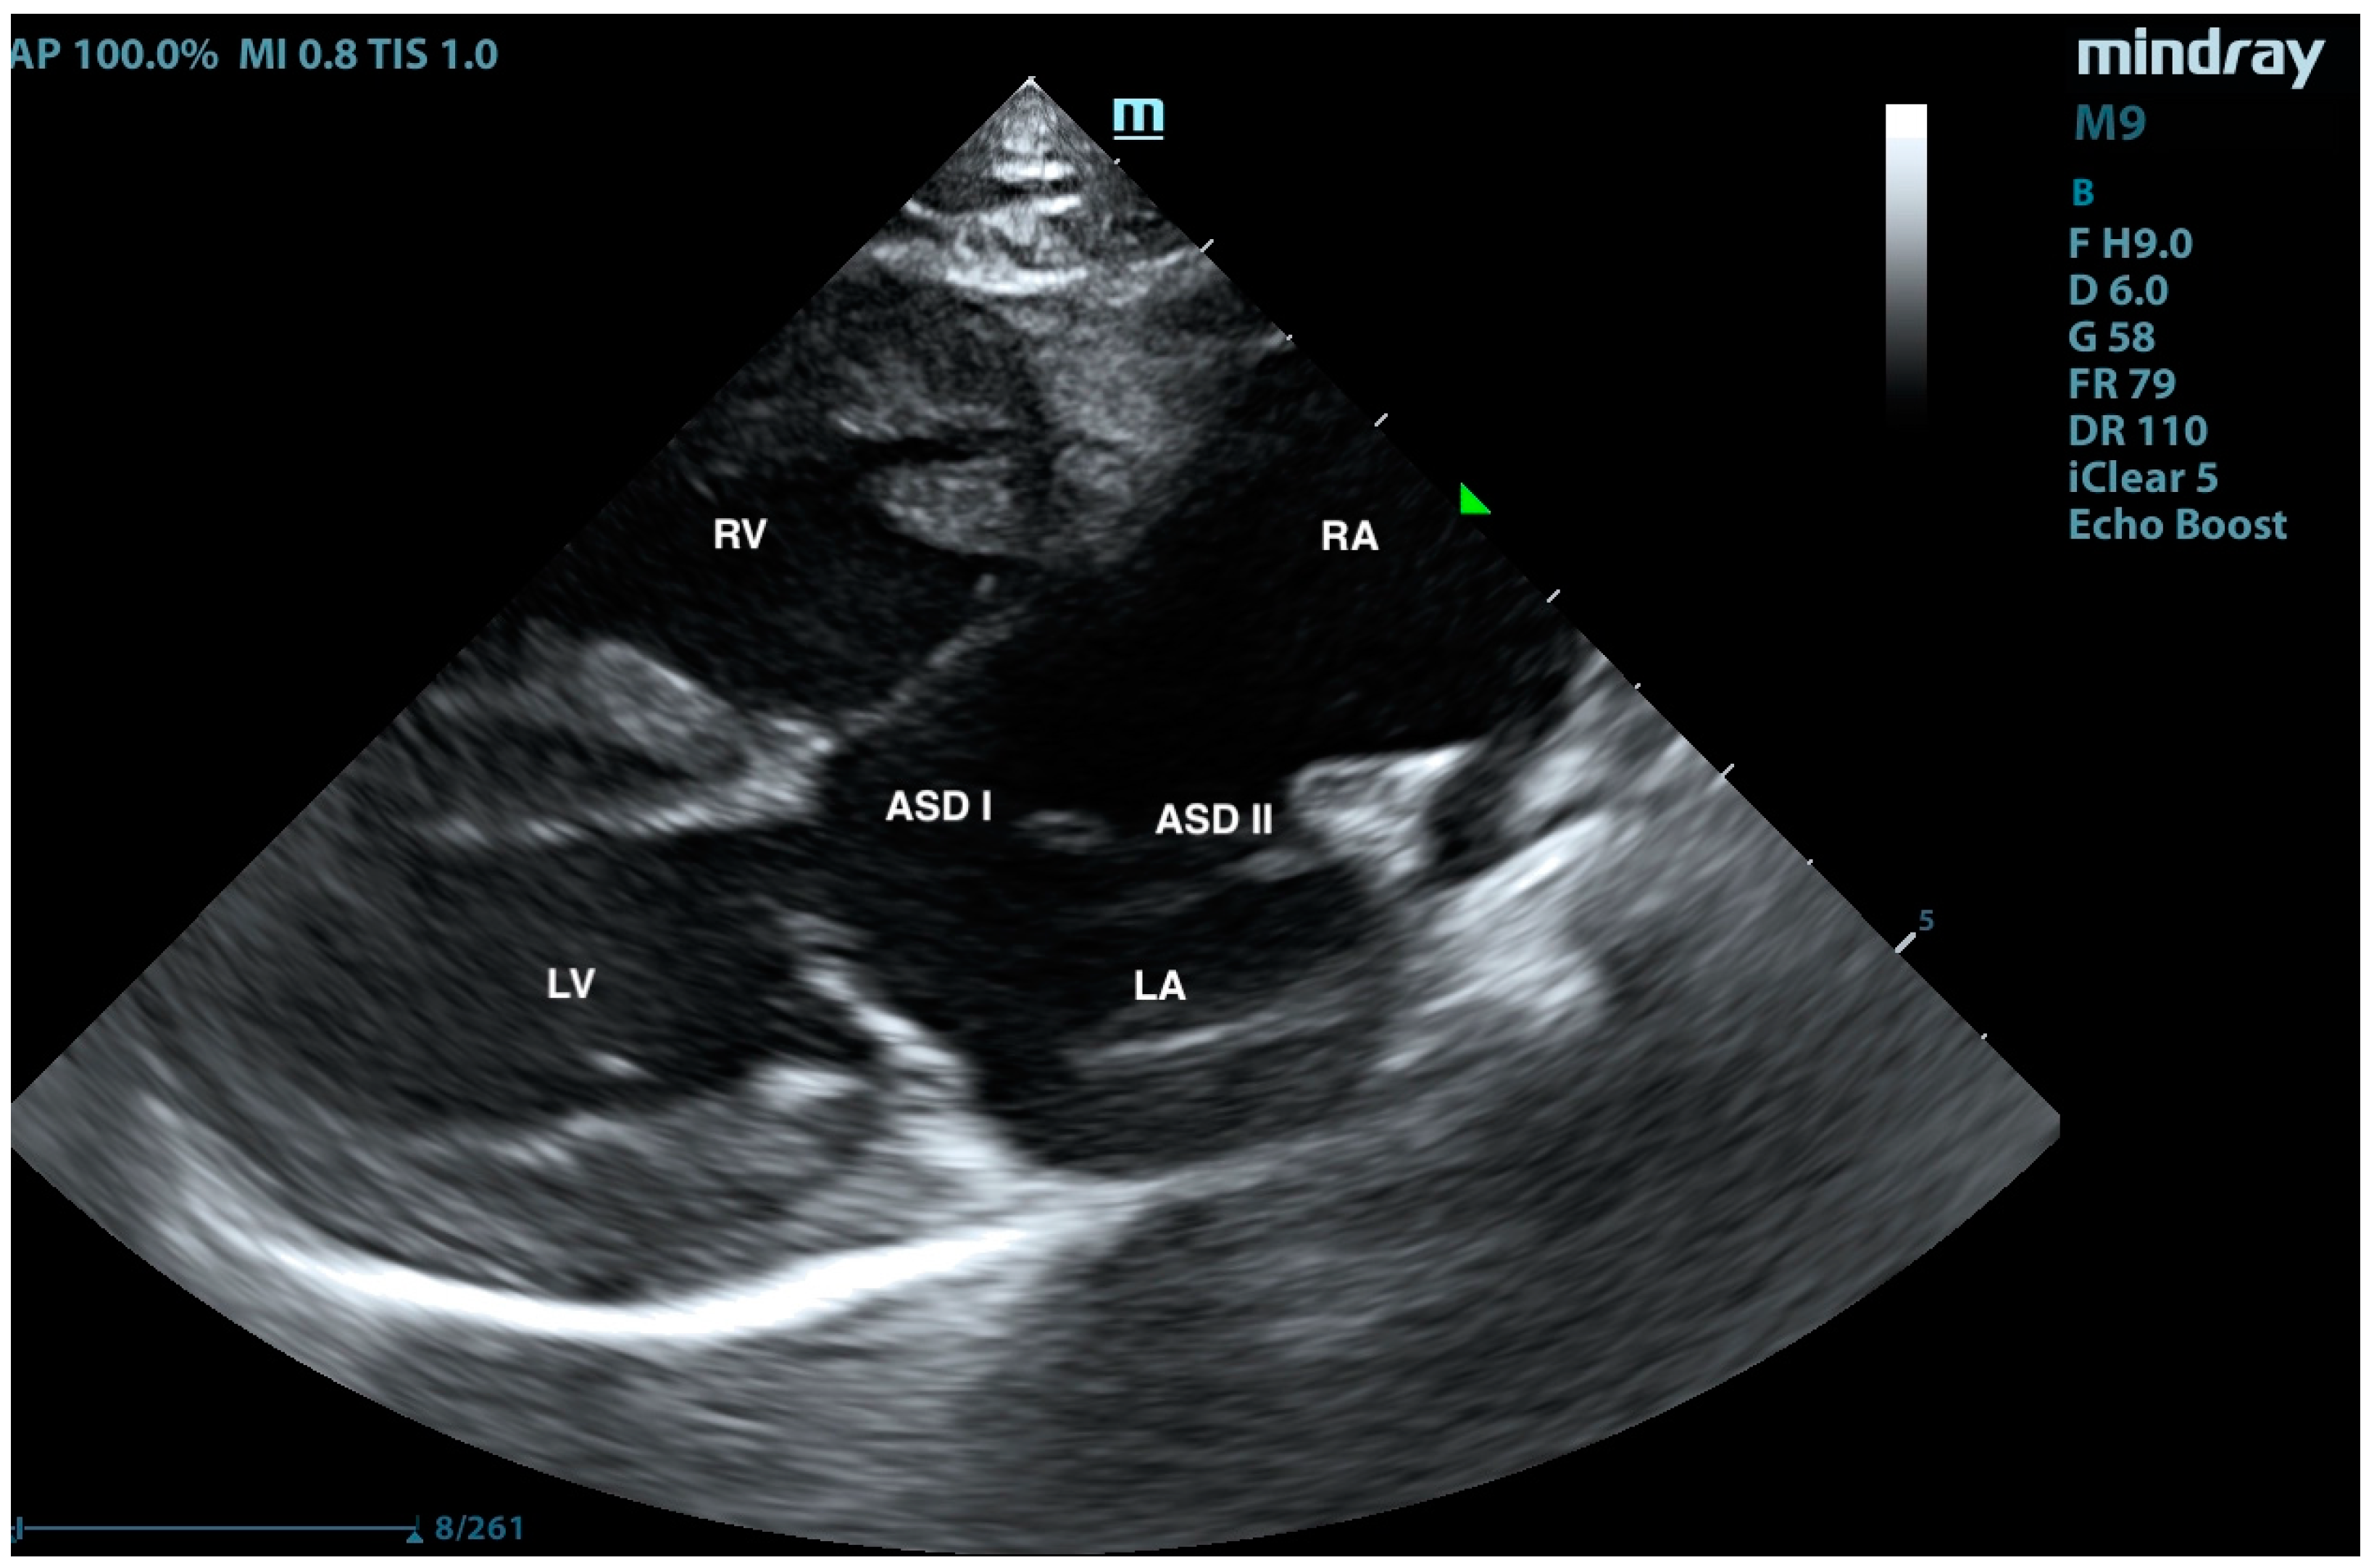

Pulmonary Artery Banding in a Cat with Atrioventricular Canal Defect Type A with Concurrent Muscular Septal Defect

2. Case Presentation